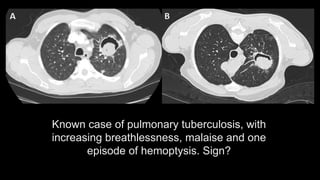

Known case of pulmonary tuberculosis, with

increasing breathlessness, malaise and one

episode of hemoptysis. Sign?

Air crescent sign/ Monod Sign of fungal ball